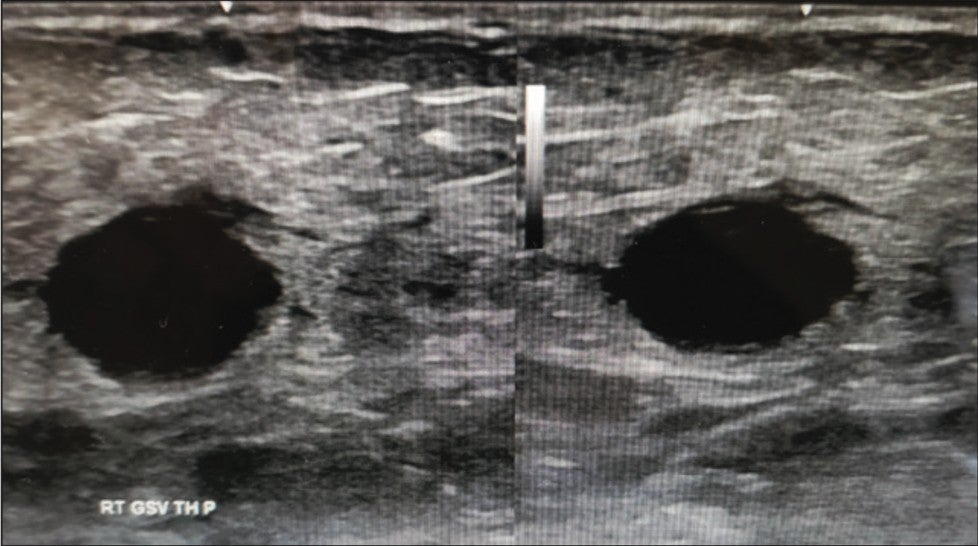

Vein diameters measured 14.1mm in the proximal GSV (Figure 3) and 12.2mm in the mid-GSV (Figure 4). CEAP class of 5.

Figure 5. Post-Varithena Treatment Rt. Proximal GSV